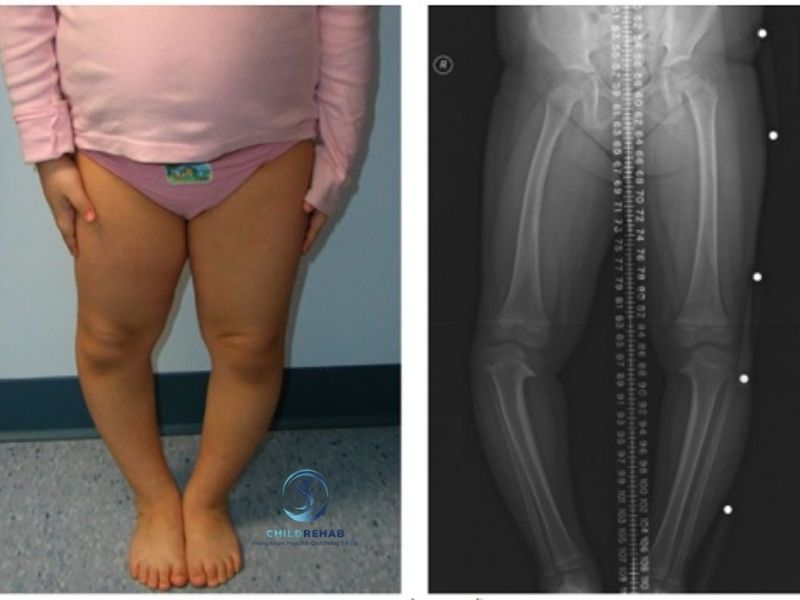

Trong quá trình phát triển của trẻ nhỏ, nhiều phụ huynh nhận thấy con có biểu hiện hai chân cong ra ngoài, đầu gối không chạm nhau khi đứng thẳng hoặc dáng đi có vẻ vòng kiềng hơn so với các bạn cùng tuổi. Không ít gia đình cho rằng đây chỉ là đặc điểm bình thường, “trẻ con ai cũng vậy”, nên thường chọn cách chờ thêm một thời gian để xem con có tự cải thiện hay không. Tuy nhiên, chân chữ O ở trẻ là tình trạng cần được theo dõi đúng cách, bởi ở một số giai đoạn đây có thể là biến đổi phát triển sinh lý bình thường, nhưng trong những trường hợp khác lại có thể liên quan đến lệch trục chi dưới hoặc các vấn đề vận động – chỉnh hình cần được đánh giá sớm.

Điều khiến phụ huynh dễ băn khoăn là tình trạng này không phải lúc nào cũng rõ ràng ngay từ đầu. Có trẻ chỉ hơi cong chân nhẹ khi mới biết đi, nhưng cũng có trẻ càng lớn càng thấy dáng đứng vòng kiềng rõ hơn, dáng đi thiếu cân đối, chạy nhảy kém ổn định hoặc mòn dép lệch bất thường. Dù nhiều trẻ không than đau, nhưng nếu chân chữ O kéo dài hoặc tiến triển rõ theo thời gian, trẻ có thể bị ảnh hưởng đến dáng đi, khả năng chịu lực của chân, sự cân đối cơ thể và hình thể vận động về lâu dài.

Điều quan trọng là cha mẹ cần hiểu rằng không phải mọi trường hợp chân chữ O đều cần can thiệp giống nhau. Có trẻ chỉ cần được theo dõi trong đúng giai đoạn phát triển, nhưng cũng có những trường hợp nên được đánh giá chuyên môn sớm để xác định xem đây là biến đổi sinh lý bình thường hay dấu hiệu của một bất thường cần hỗ trợ kịp thời. Việc phát hiện đúng thời điểm sẽ giúp trẻ có cơ hội phát triển hệ vận động cân đối hơn, đồng thời hạn chế những ảnh hưởng lâu dài về tư thế và trục chân.